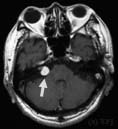

それほど大きくない聴神経鞘腫の一例 (患者さんの許可をえて画像を掲載)